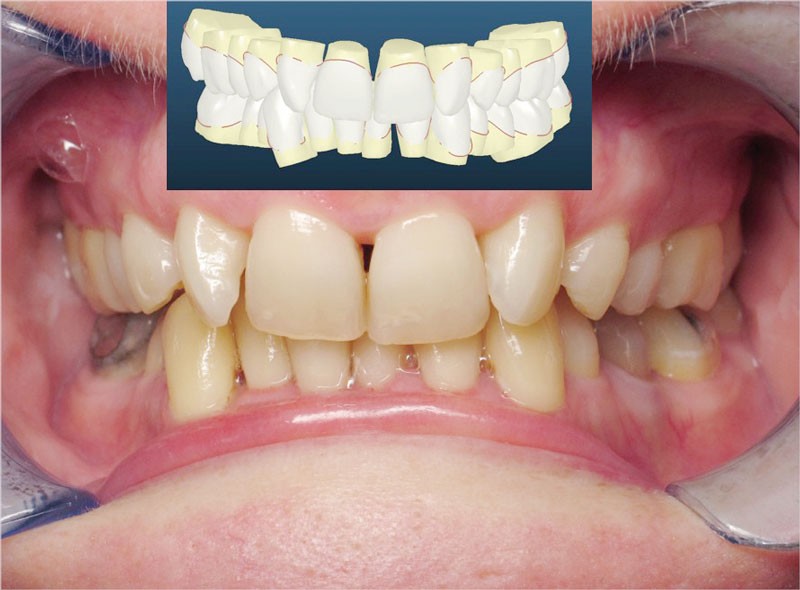

Cas n° 2

Nous lui avons donc proposé un traitement d’alignement avec maintien des 14 et 24 en position de 13 et 23 et optimisation du torque pour favoriser un développement des arcades et chercher à améliorer le sourire et le soutien labial.

La patiente donne son accord pour un appareillage Damon Insignia métal qui permet une individualisation complète des brackets dans les 3 sens de l’espace.

Un appareillage Damon métal a été mis en place, réalisé à partir d’un set up numérique Insignia pour obtenir un contrôle précis des torques et de la forme d’arcade et réduire le temps de finition grâce à un collage indirect très précis.

L’objectif, en utilisant la technique Insignia est de réduire le temps de traitement de 28 à 18 mois avec 12 rendez-vous (fig. 5 à 14).